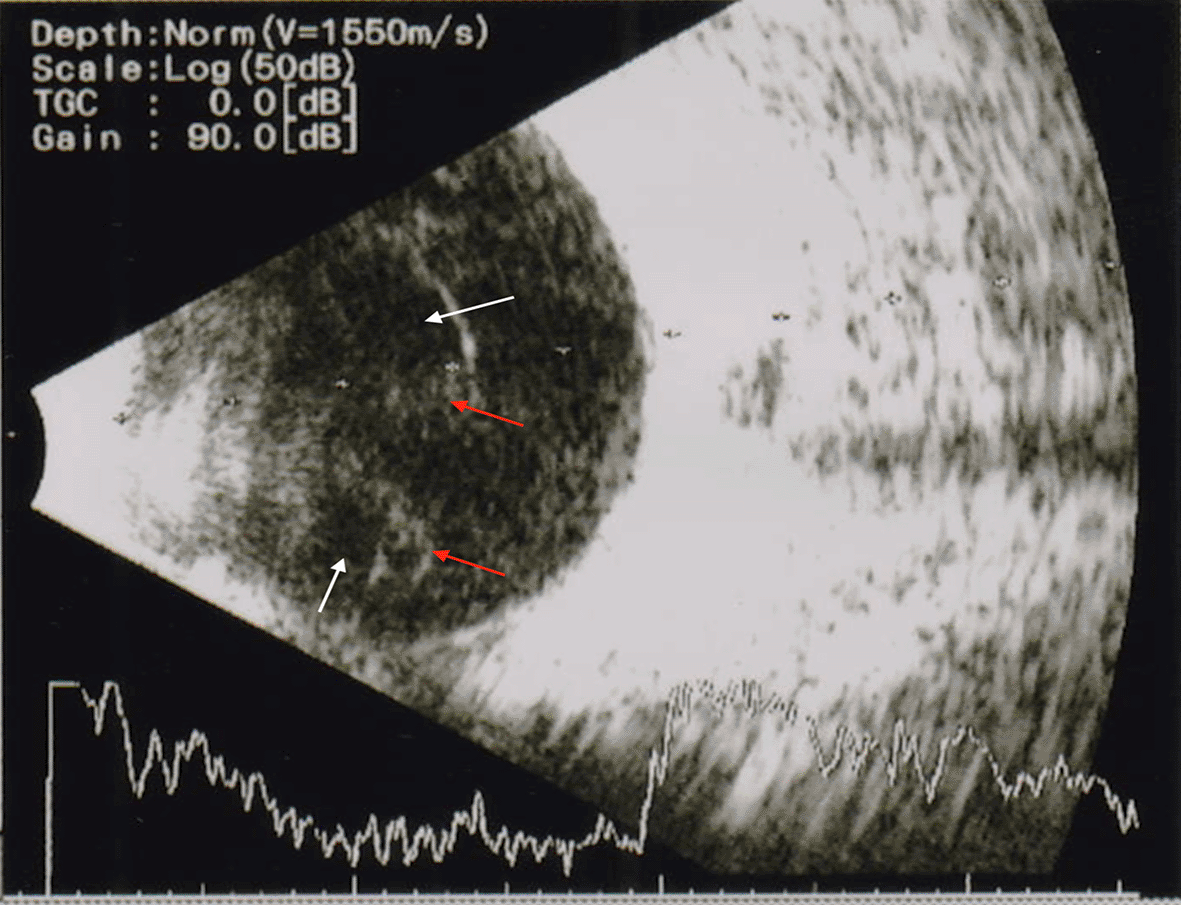

On ocular examination, she only perceived light with an inaccurate ray’s projection in the left eye and 6/6 in the right eye. There were tense lid edema and proptosis (Figure 1) with severely restricted eye movement in all gazes. There were severely chemosed conjunctiva, circumcorneal congestion and edematous cornea, and no further visibility of the anterior and posterior segments. A B-scan ultrasonogram (USG) showed moderate hyperechogenic shadows with cavitations in the vitreous cavity, which disappeared at low gain with attached retina and increased choroidal thickness in the left eye (Figure 2). So diagnosed as a case of left-sided orbital cellulitis with endogenous endophthalmitis (EE).

During an eye examination, she perceived light with an inaccurate projection of rays in the left eye, while the right eye had 6/6 vision. There was moderate proptosis, eyelid and conjunctival chemosis, ciliary congestion with corneal edema, and no other view of both segments of the left eye (Figure 1). A clinical diagnosis of orbital cellulitis with endogenous endophthalmitis (EE) was made, and B-scan USG findings were suggestive of endophthalmitis (Figure 2). Uncontrolled diabetes mellitus, use of catheters, low neutrophil count, immunosupressed patients, and patients on chemotherapy were predisposed to EE. Despite reports of anecdotal cases, pregnancy is not associated with higher EE rates.2 These cases had a history of either septic abortion, handling of an intrauterine device, or IV fluid infusion.2 Our patient received intravenous injections of dextrose infusion, fresh blood transfusion, and broad-spectrum injectable antibiotic as her initial blood reports showed 7.2 g/dL Hb (normal: 10–14 g/dL) and 12,300/μL total white blood cells count (normal: 4,000–11,000/μL) with 82% neutrophil (normal: 40–75%), which her gynecologist prescribed. Her other hematological and urine analysis, including blood and urine cultures, were negative for any organisms, and there were no systemic foci of infections.